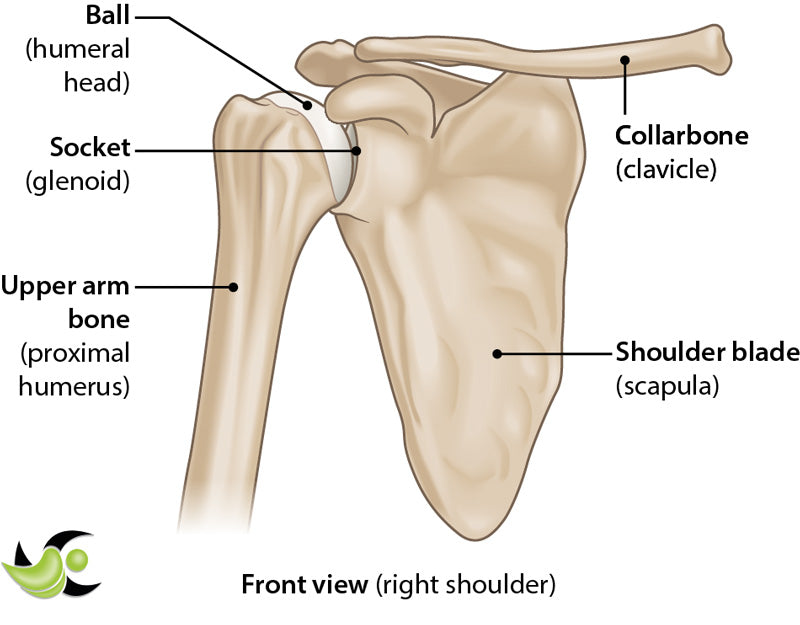

Articular cartilage covers the surface of a bone where it meets with another bone at a joint. In the shoulder, there is articular cartilage covering the head of the humerus (arm bone) and the glenoid (socket bone) where they come together to form the glenohumeral joint. There is also articular cartilage at the ends of the acromion and the clavicle where they meet to form the AC joint. This cartilage is important to provide both a smooth, lubricated surface for joint articulation and to help distribute load to reduce stress on your bones.